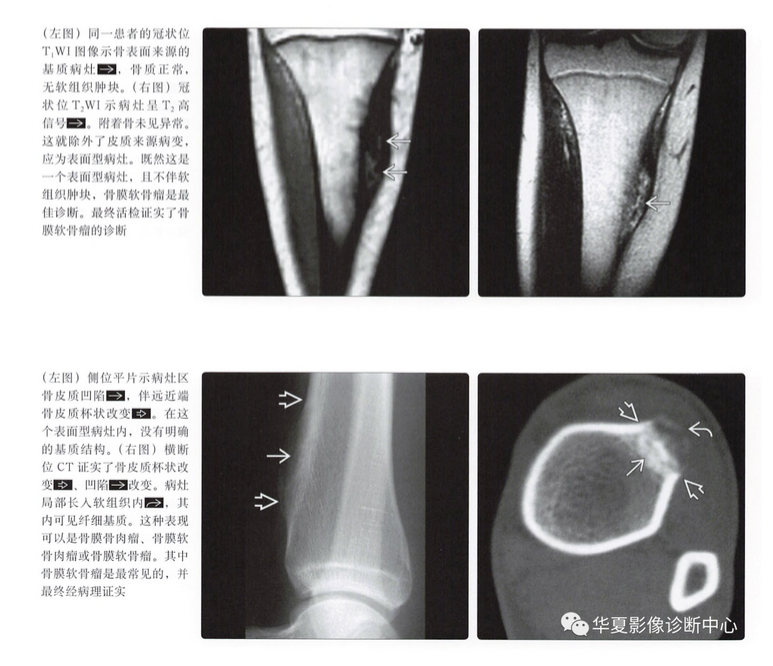

MR表现

- 病灶的结节状形态

- T1上等或低信号

- T2上高信号

- 不均匀强化,通常呈边缘强化

- 髓内累及(20%)

- 髓内水肿(20%)

- 不规则软组织肿块(30%)